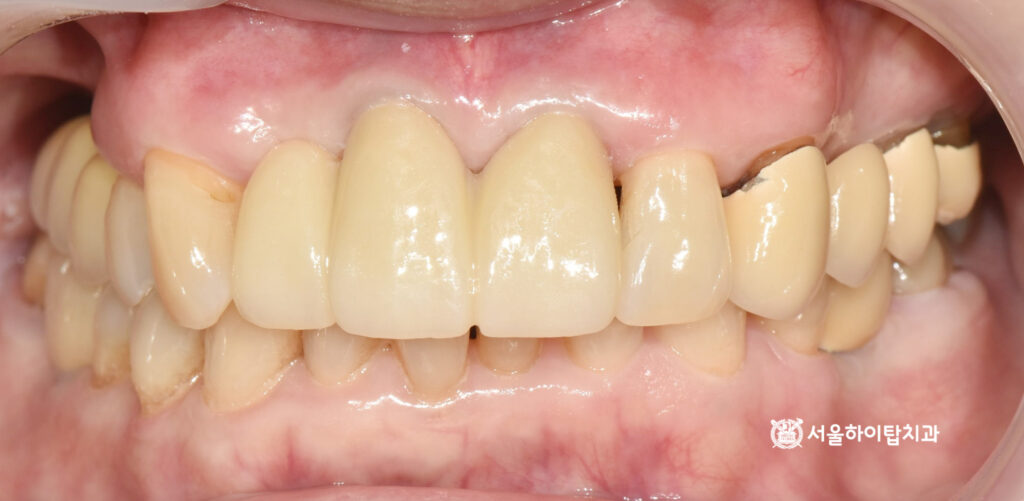

6. 최종 결과

만수동 치과 에서최종 완성된

모습을 준비한 자료를 통해

보여드리겠습니다.

정밀한 인상 채득 과정을 거쳐

맞춤형 지르코니아 크라운이

장착된 모습입니다.

장착 후에는 교합 관계와

치은 라인을 세밀하게 확인하여,

심미성과 기능이 모두 조화롭게

회복된 것을 확인할 수 있습니다.

특히 앞니 부위는 발음과 표정,

심미적 균형이 중요한 부위이므로,

최종 크라운이 주변 자연치와

자연스럽게 조화를 이루는지 세심하게

체크하는 과정이 필요합니다.